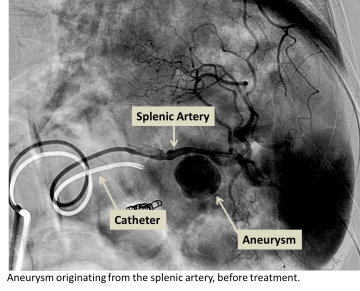

Splenic artery aneurysm before treatment